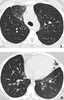

Central bronchiectasis

Bronchiectasis is a disease in which there is permanent enlargement of parts of the airways of the lung. Symptoms typically include a chronic cough with mucus production. [Source: Wikipedia ]